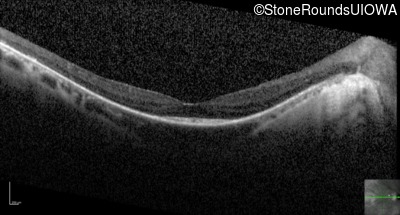

Optical Coherence Tomography - Right - 20/30 +2

Exemplar / OCT Stack

OCT Stack